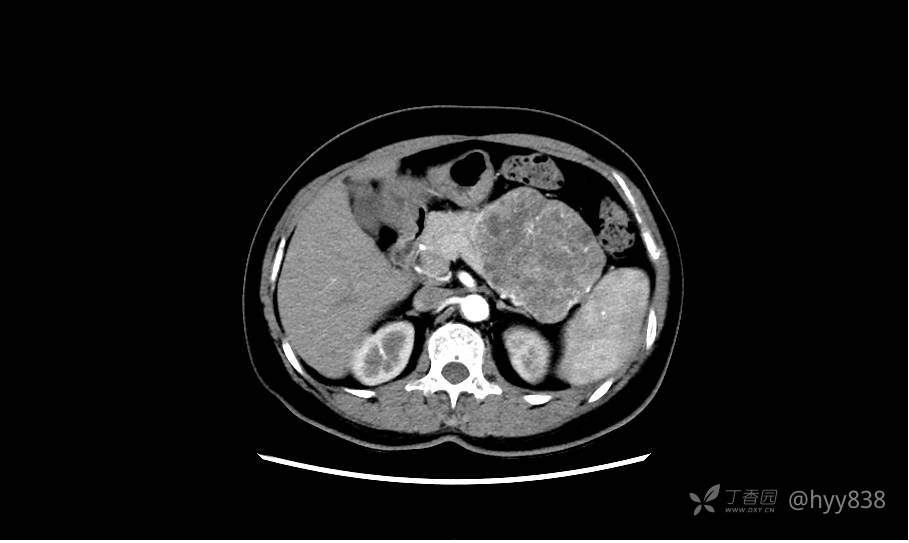

静脉期(机器故障---延迟期了)